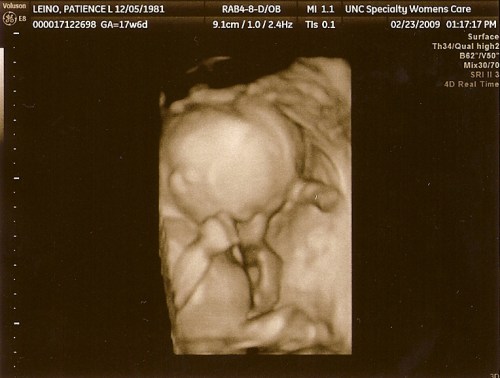

Today was our second Level 2 ultrasound on Baby Girl Leino. She had herself completely balled up for most of the sonogram with hands hiding her face – much like her older brother. At least the Leino kids are consistent! Our sonogram technician was incredibly thorough, explaining everything he was looking at as he went. When the exam first began, she had her legs properly crossed at the ankles. Jordan was so proud, saying “That’s my girl!” He’s going to be an incredible father.

Our sonogram tech spent most of his time getting a good look at her brain and heart. Once he finally had a good view of her heart, Jordan and I felt a weight lifted as we saw four perfectly-formed chambers pumping away. No signs of cardiac defects! Praise the Lord! He spent an hour measuring all her bones and organs while trying very hard to get a good 4D view of her face. The doctor then came back to review the ultrasound findings with us. Thankfully, no structural anomalies were found. Our darling currently measures two days ahead of schedule, while her belly measures a full week ahead. She’s certainly been eating well. We have our third Level 2 in May at 30 weeks gestation for another look at all her organs, bones, and growth. We’re hoping that she’ll cooperate with us for a good picture then.